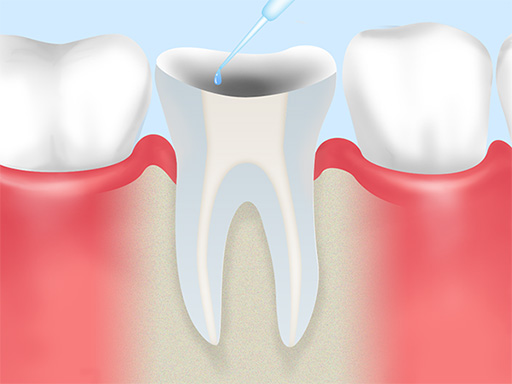

根管内の洗浄 -

神経や感染した内部を掃除し、薬剤で根管内を徹底的に洗浄・殺菌します。

根管充填 -

根管内を清掃・乾燥させた後、隙間なくお薬(充填材)を詰めて封鎖します。